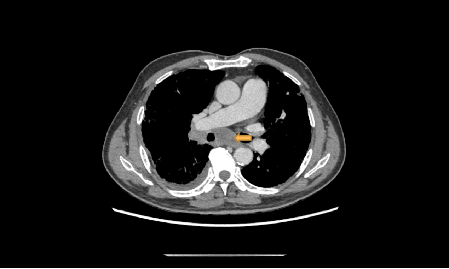

一名70岁的男性患者因“反复咳嗽、咳痰3年,加重2月余”到我院就诊,胸部增强CT提示双肺间质性肺炎、右肺下叶肺癌并纵隔淋巴结转移。

右主支气管狭窄,肺间质纤维化(黄色箭头为隆突下淋巴结肿大)

黄色箭头为隆突下淋巴结肿大